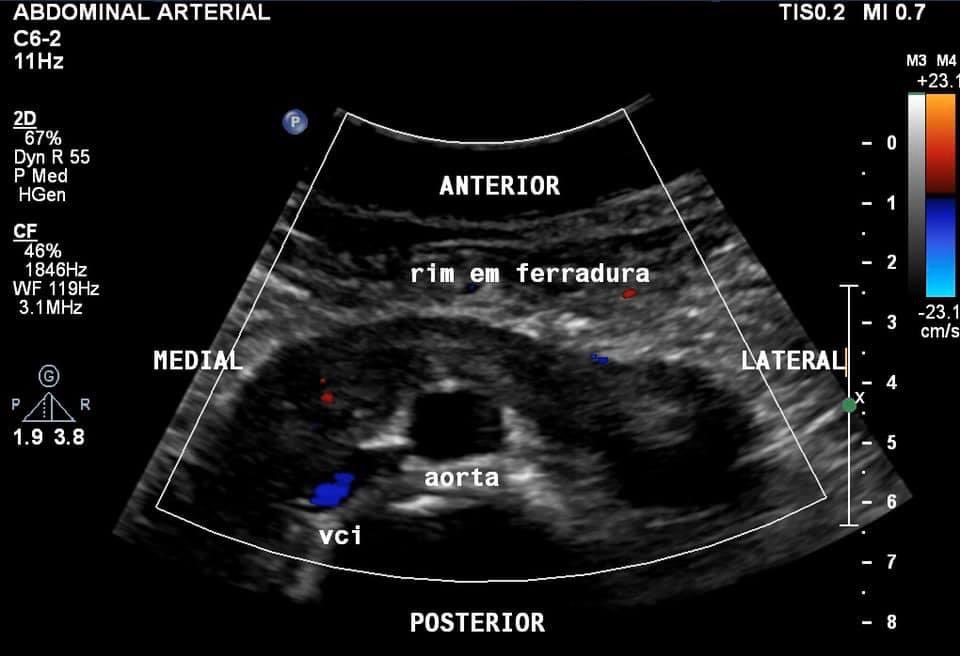

Incidental finding on aortoiliac examination. W, 62 years old, dyslipidemic and hypertensive. Artery emerging from the anterior wall of the infrarenal aorta, and in a caudal-cranial direction - RI: 0.67.

DUS: horseshoe kidney.

#dopplervascular